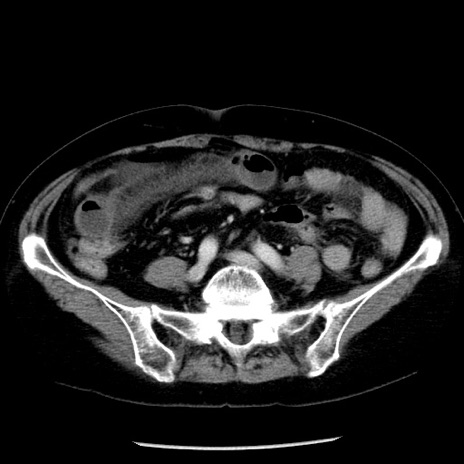

症例13(横断像)

【症例】70歳代女性

【主訴】腹痛、嘔吐

【現病歴】15時間程前(昨晩)より腹痛あり。今朝になっても症状の改善なく、嘔吐あり。腹痛も増悪あり、救急外来受診。

【既往歴】子宮癌全摘術後

【身体所見】意識清明、BP 121/72mmHg、P 74bpm、SpO2 100%(RA)、腹部:平坦・軟、腸雑音ほぼ聴取せず。下腹部・心窩部・臍左上に圧痛あり。反跳痛なし。

【データ】WBC 10600、CRP 0.15